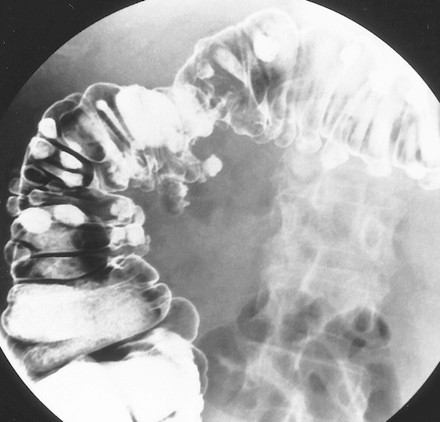

3.4. Bệnh túi thừa

Túi thừa đại tràng là tình trạng mắc phải, trong đó niêm mạc và màng cơ thoát vị qua chỗ yếu của lớp cơ, tạo thành túi lộn ra ngoài. Người có túi thừa đại tràng hiếm gặp ở người dưới 25 tuổi, thấy ở 50% người trên 75 tuổi. Phim X quang thường có thể thấy các túi thừa là các túi chứa đầy khí nằm song song với lòng đại tràng. Kích thước các túi thường 5-10mm. Chúng có thể ở bất cứ chỗ nào của đại tràng (Hình 21), nhưng thường thấy rất nhiều ở đại tràng sigma.

Viêm túi thừa thường có thủng và áp xe khu trú trong thành hoặc áp xe quanh đại tràng. Viêm túi thừa là biến chứng xảy ra trong 20% bệnh nhân có túi thừa. Biến chứng của viêm túi thừa gồm tắc ruột, chảy máu, viêm phúc mạc, và tạo thành đường rò hoặc đường xoang (sinus: các đường hầm không có lỗ mở ra ngoài hoặc vào tạng rỗng). Các đường xoang có thể tạo thành các ổ áp xe lớn ở trong khoang phúc mạc hoặc khoang sau phúc mạc. Các đường rò thường tới bàng quang (Hình 22), âm đạo, hoặc da, hoặc các cơ quan khác trong tiểu khung. Dấu hiệu xác nhận của viêm túi thừa khi chụp baryt bao gồm các túi thừa biến dạng, trào thuốc ra khỏi lòng đại tràng (đôi khi chạy song song với lòng đại tràng gọi là dấu hiệu đường đôi), hiệu ứng khối của áp xe (hẹp lòng đại tràng thuôn, nhẵn).

Hình 21. Hình cản quang kép tư thế đứng cho thấy vô số túi thừa có bờ nhẵn ở đại tràng xuống. Lưu ý, các mũi tên chỉ polyp có cuống (mũi tên thẳng chỉ đầu, mũi tên cong chỉ cuống).